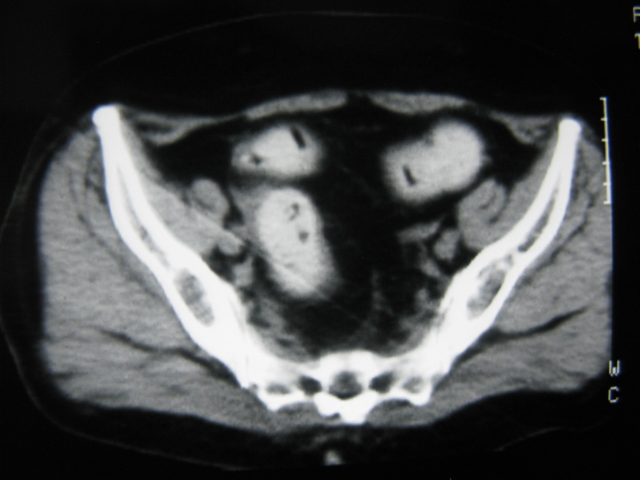

患者,女,64岁,2002年诊断为宫颈癌,当时只做过放,化疗。现在诊断:(1)宫颈癌。(2)直肠癌。请同道们讨论,探讨。另外肠壁为啥密度这么高,ct值约112hu。患者没有做过增强和造影。

高密度的不是肠管影,是肠管内的粪便影

患者直肠病变,排便不畅,粪便硬结造成,更高密度如钡灌肠者都可出现

硬结粪便能有如此高密度影?

我也碰到过几例,最离奇的一例是全结肠呈造影样高密度,患者直肠癌(首次发现),以往没有吃药,只有约半年时间长的胃纳差,排便不畅(据患者说每次大便只能拉出少许黄水)

不一定有意义,可清洁灌肠后复查